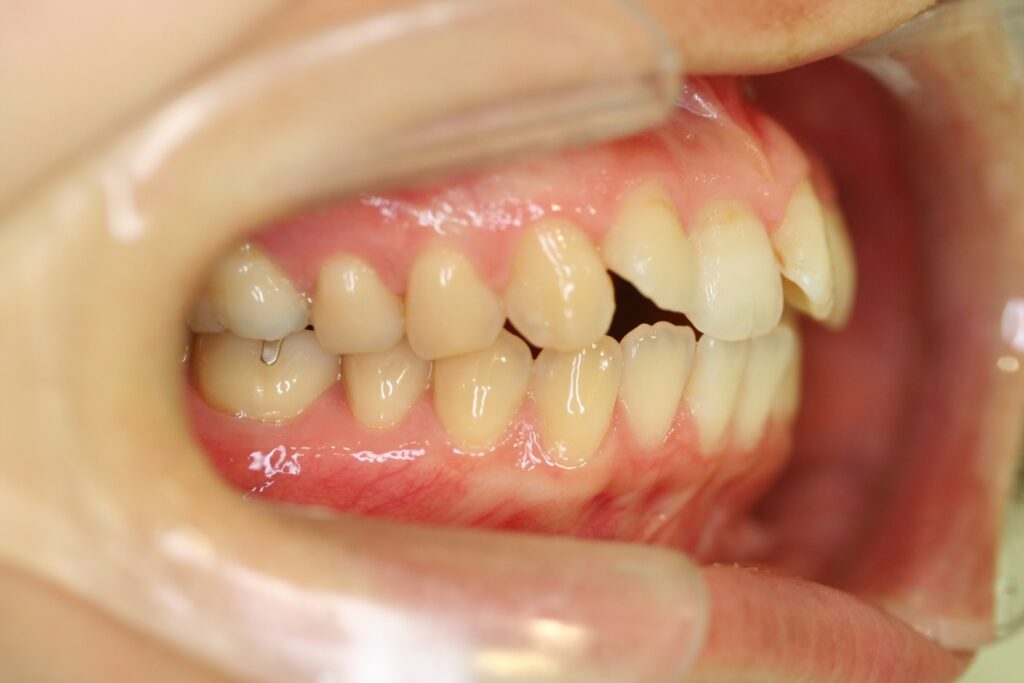

治療実績(症例) アライナー矯正 症例1 上顎前突症例 症例2 上下顎前突症例 症例3 叢生 症例4 開咬 症例5 開咬(外科的矯正治療) アライナー矯正 Post Share Hatena Line RSS feedly Pin it note 1.主訴2.診断名3.初診時年齢4.治療に用いた主な装置とオプション5.抜歯部位6.治療期間・通院回数7.総額と費用内訳総額相談検査・診断料調整料4,000円8.リスク・副作用 治療前 治療中 治療後